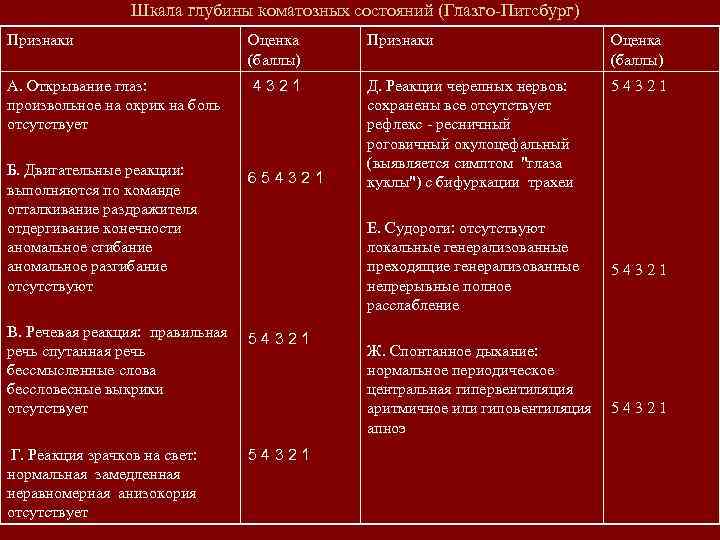

Шкала глубины коматозных состояний (Глазго-Питсбург) Признаки Оценка (баллы) А. Открывание глаз: произвольное на окрик на боль отсутствует 4321 54321 Б. Двигательные реакции: выполняются по команде отталкивание раздражителя отдергивание конечности аномальное сгибание аномальное разгибание отсутствуют 654321 Д. Реакции черепных нервов: сохранены все отсутствует рефлекс - ресничный роговичный окулоцефальный (выявляется симптом "глаза куклы") с бифуркации трахеи В. Речевая реакция: правильная речь спутанная речь бессмысленные слова бессловесные выкрики отсутствует 54321 Г. Реакция зрачков на свет: нормальная замедленная неравномерная анизокория отсутствует 54321 Е. Судороги: отсутствуют локальные генерализованные преходящие генерализованные непрерывные полное расслабление Ж. Спонтанное дыхание: нормальное периодическое центральная гипервентиляция аритмичное или гиповентиляция апноэ 54321

Шкала глубины коматозных состояний (Глазго-Питсбург) Признаки Оценка (баллы) А. Открывание глаз: произвольное на окрик на боль отсутствует 4321 54321 Б. Двигательные реакции: выполняются по команде отталкивание раздражителя отдергивание конечности аномальное сгибание аномальное разгибание отсутствуют 654321 Д. Реакции черепных нервов: сохранены все отсутствует рефлекс - ресничный роговичный окулоцефальный (выявляется симптом "глаза куклы") с бифуркации трахеи В. Речевая реакция: правильная речь спутанная речь бессмысленные слова бессловесные выкрики отсутствует 54321 Г. Реакция зрачков на свет: нормальная замедленная неравномерная анизокория отсутствует 54321 Е. Судороги: отсутствуют локальные генерализованные преходящие генерализованные непрерывные полное расслабление Ж. Спонтанное дыхание: нормальное периодическое центральная гипервентиляция аритмичное или гиповентиляция апноэ 54321

Примечание: Общая оценка Трактовка При спонтанном дыхании 35 баллов - 7 баллов нет комы- смерть мозга При ИВЛ (не оцениваются “речевые реакции” и “спонтанное дыхание”) 25 баллов - 5 баллов нет комы - смерть мозга

Примечание: Общая оценка Трактовка При спонтанном дыхании 35 баллов - 7 баллов нет комы- смерть мозга При ИВЛ (не оцениваются “речевые реакции” и “спонтанное дыхание”) 25 баллов - 5 баллов нет комы - смерть мозга